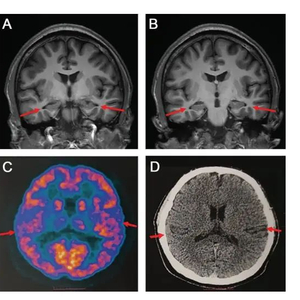

论文中表示,医院为患者做了多种检查,包括当前用于诊断阿尔兹海默病的最权威手段——脑脊液指标检测和PET扫描,患者还接受了多种量表测试。扫描影像等显示,患者存在轻度的脑萎缩等症状,部分脑脊液指标也存在异常,最终患者被临床诊断为阿尔兹海默症患者。